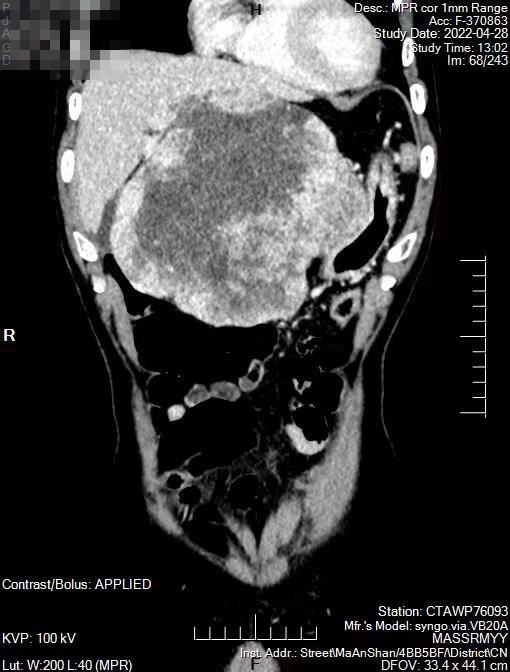

日前,一向身體健康的董先生感覺腹脹,主訴“肚子鼓起來了”。在家人的陪伴下,董先生來到市人民醫(yī)院東院(秀山醫(yī)院)普外綜合科診治。醫(yī)生查體發(fā)現(xiàn)董先生腹腔內(nèi)有腫塊,做CT檢查顯示一個(gè)約20cm腫塊位于肝胃間隙,血供豐富,推擠肝臟、壓迫胃壁。這樣的腫塊生長迅速,常常危及生命。

普外綜合科團(tuán)隊(duì)完善相關(guān)檢查后,為董先生制定詳盡的手術(shù)方案。術(shù)中驗(yàn)證了CT檢查所見的情況,腫塊上布滿了血管,幾乎占滿了整個(gè)上腹部,部分已侵犯胃壁及大網(wǎng)膜。情況十分危險(xiǎn),巨大的腫塊可隨時(shí)引起出血、腫瘤破裂、肝臟或腸道損傷等并發(fā)癥。手術(shù)團(tuán)隊(duì)小心謹(jǐn)慎地分離周圍組織,斷扎腫瘤血管,經(jīng)過“步步驚心”謹(jǐn)慎細(xì)致的剝離和嫻熟技巧,終于將腫瘤及部分胃壁大網(wǎng)膜完整切除。術(shù)后董先生恢復(fù)很快,他笑著說道:“現(xiàn)在吃東西很香,肚子大小正常了,你們可真是巧手??!”